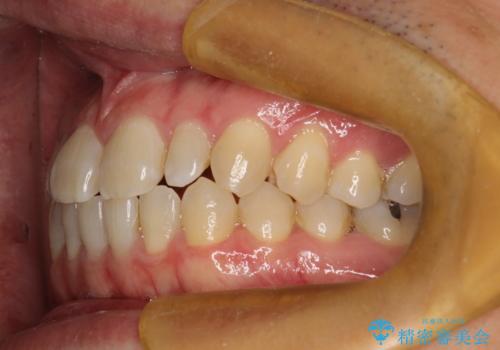

前歯の隙間 インビザラインにて整った歯並びへ

- 前歯の隙間が気になるとのことで来院されました。

インビザラインにて矯正治療を行うこととしました。

下の歯と歯の間にわずかに隙間をつくり、上の前歯の隙間を閉じました。